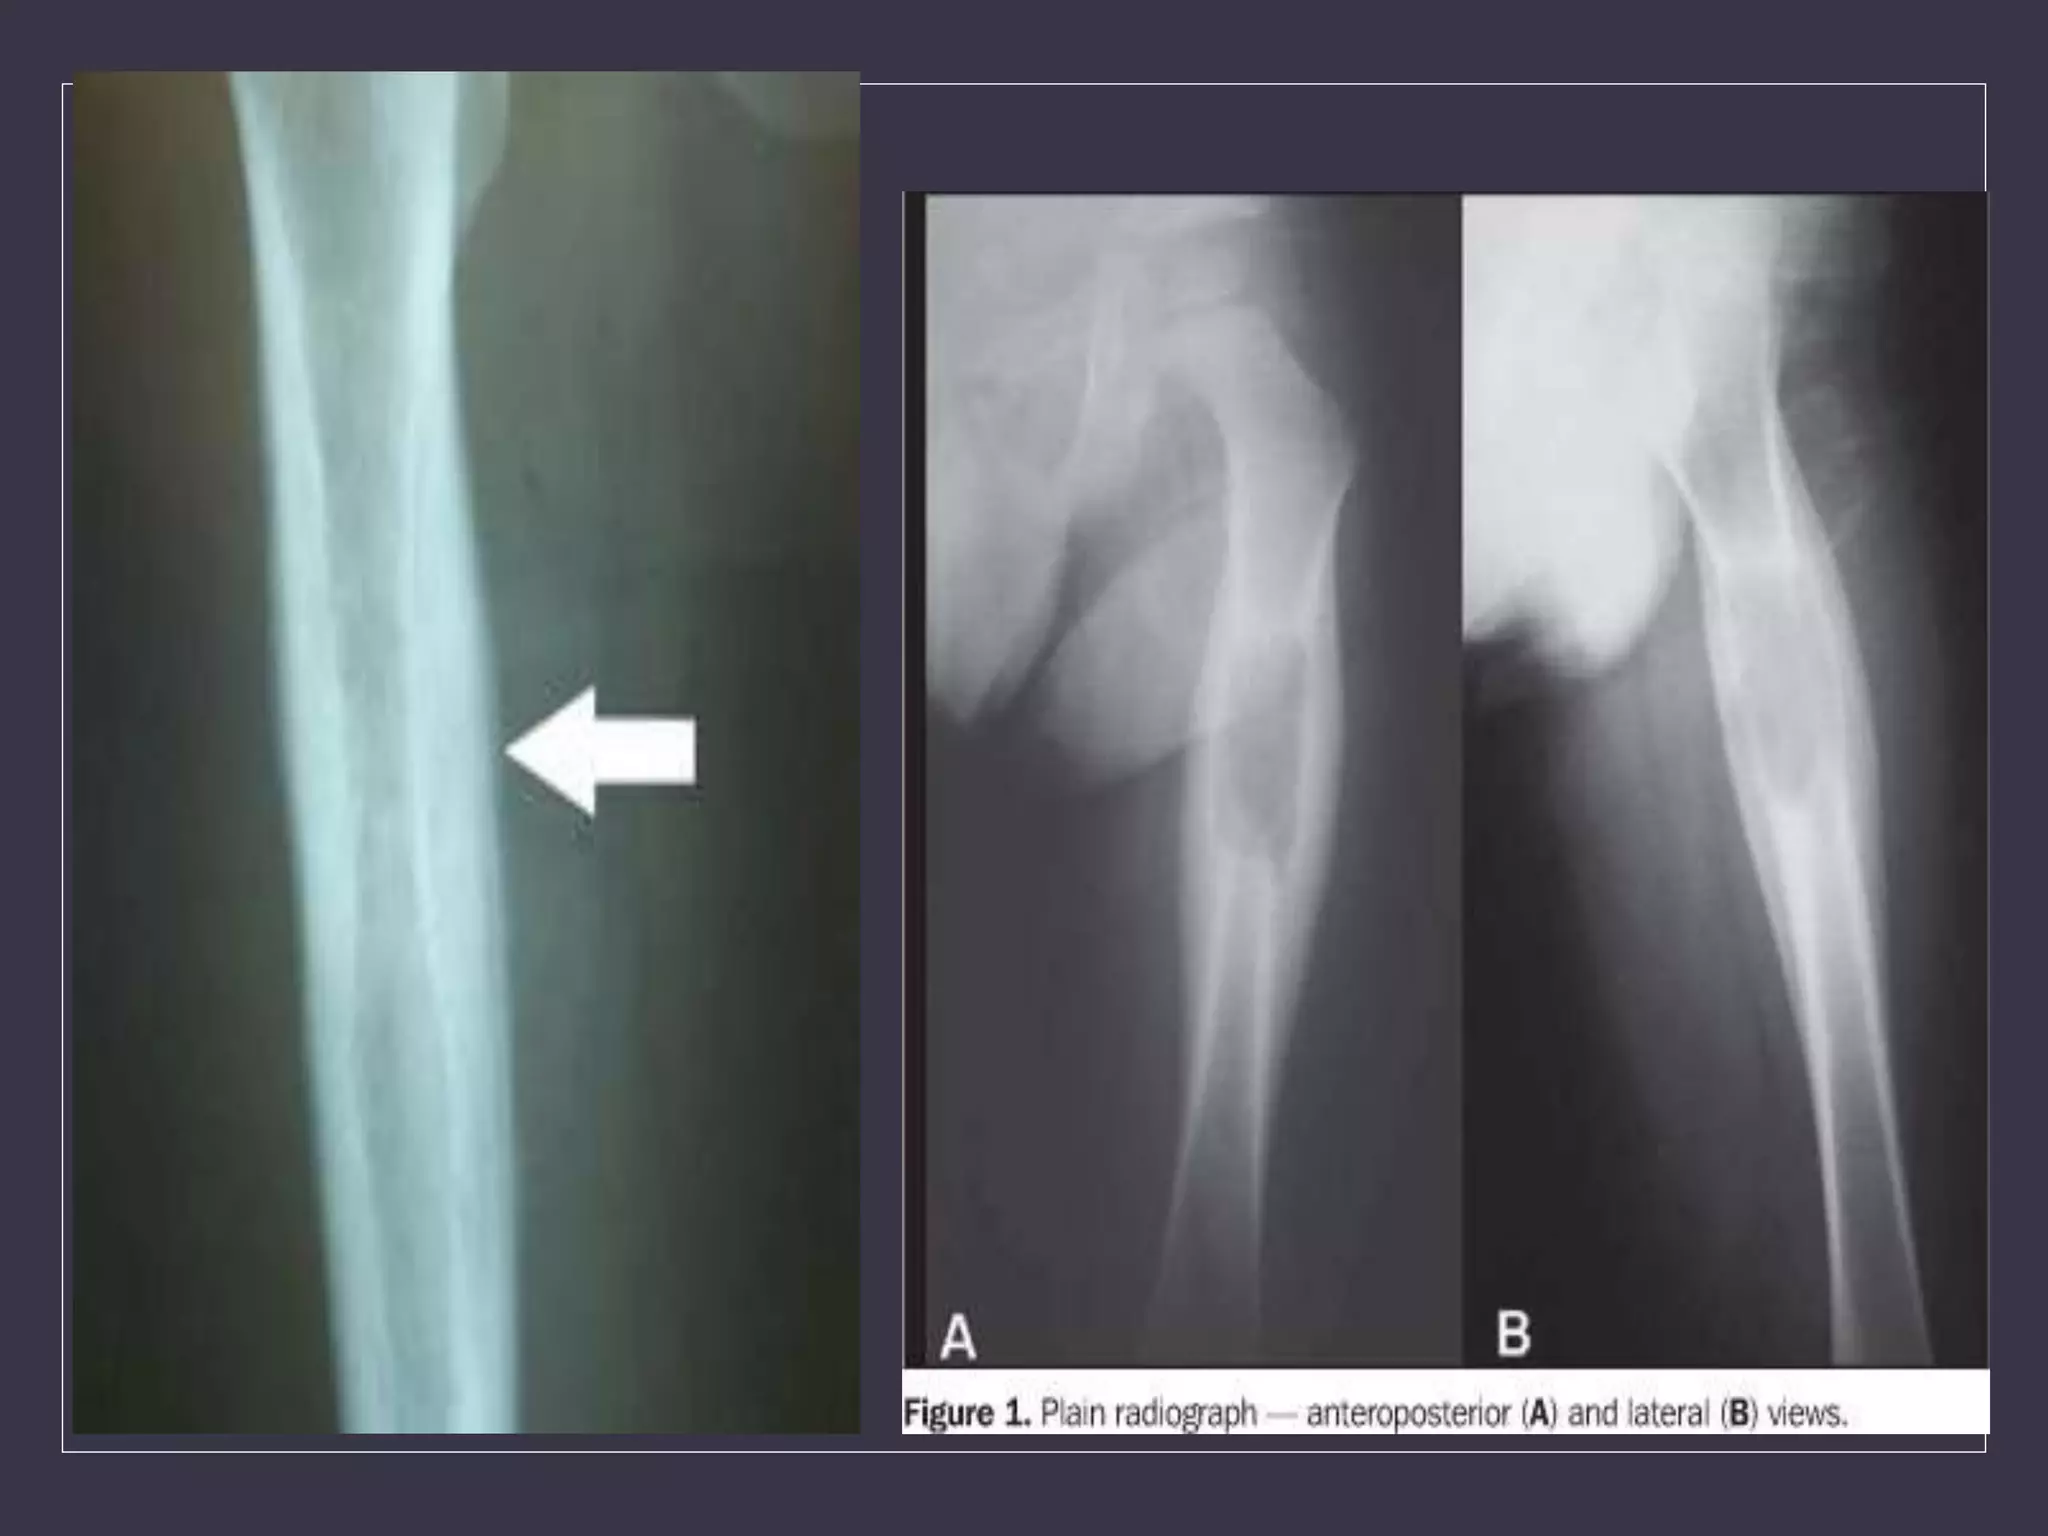

• An 11 year old boy presents with h/o pain

and diffuse bony swelling over the mid

shaft of his right fibula since last one

month.

• The mother gives h/o intermittent fever and

redness at the site of pain.

• He also has LOW and LOA.

X-Ray findings

• Usually show an area of bone destruction which,

unlike osteosarcoma, is predominantly in the mid-

diaphysis.

• New bone formation may extend along the shaft and

sometimes appears as fusiform layers of bone

around the lesion – ‘onion-peel’ effect.

• Often the tumour extends into the surrounding

tissues, with radiating streaks of ossification and

reactive periosteal bone at the proximal and distal

margins.

• The ‘sunray’ appearance and Codman’s triangle.